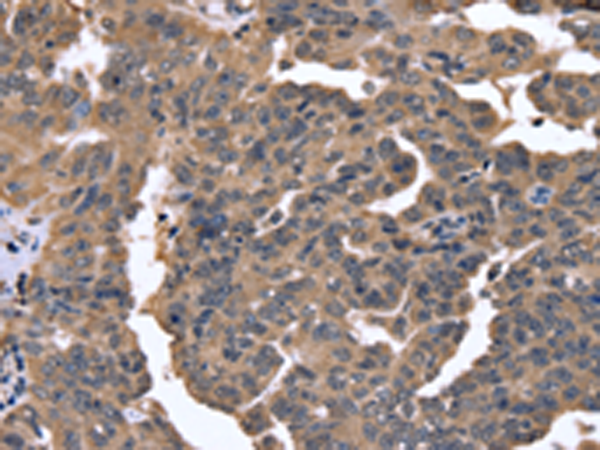

分类: 科研抗体货号: P08354别名: 87U6; ARCND1应用: IHC反应种属: Human, Mouse, Rat